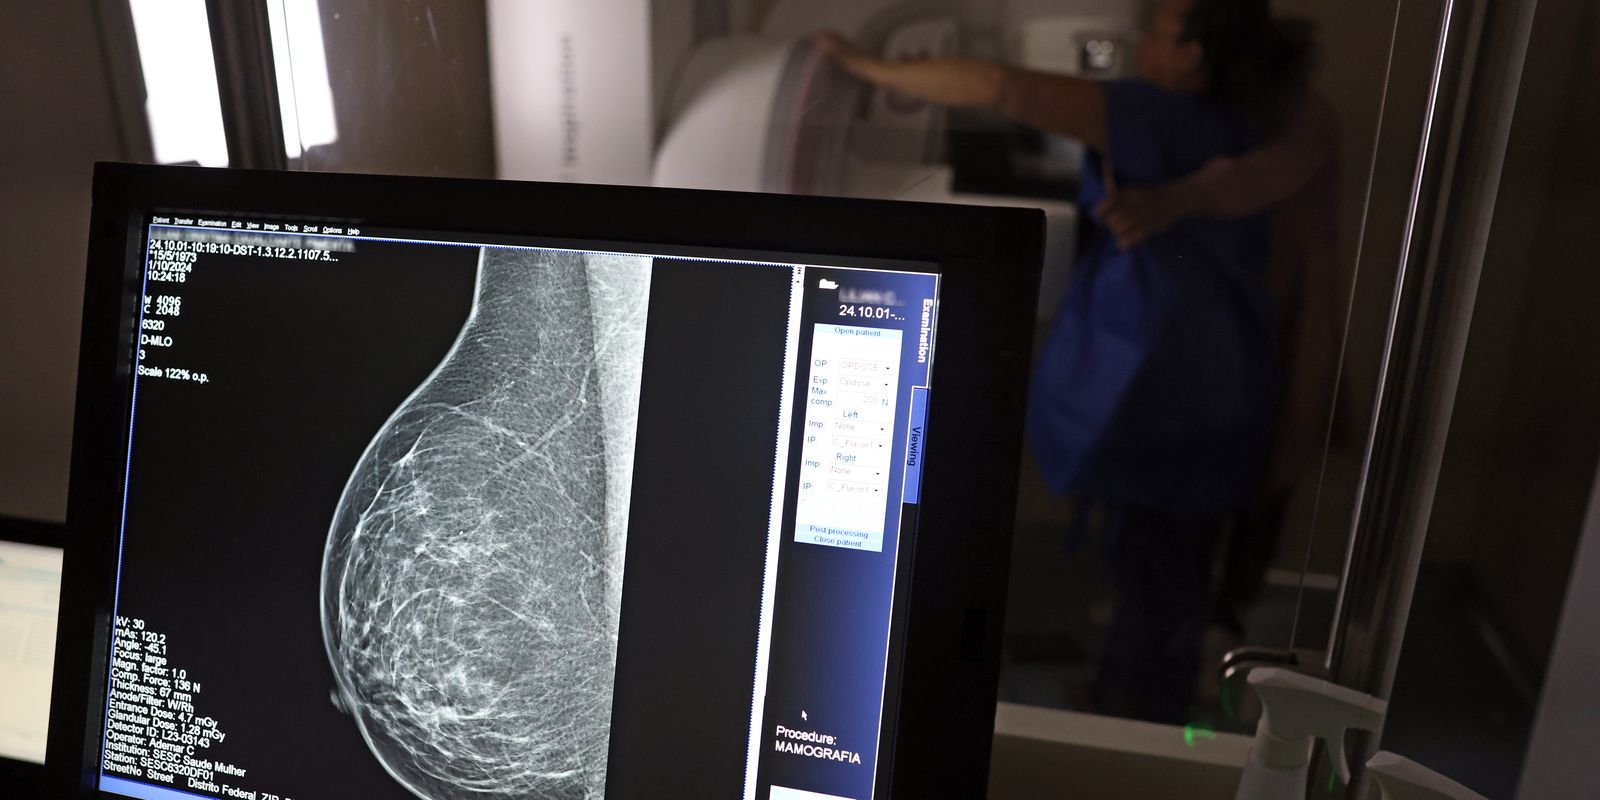

Falta de acesso a mamógrafos limita prevenção do câncer de mama

No mês de conscientização sobre o câncer de mama, um relatório destaca a importância de acesso igualitário ao rastreamento e tratamento da doença. Segundo o Atlas da Radiologia no Brasil, do Colégio Brasileiro de Radiologia e Diagnóstico por Imagem (CBR), o acesso aos mamógrafos ainda é um desafio.

O país tem 6.826 equipamentos registrados, sendo 96% em funcionamento. Metade deles está disponível no Sistema Único de Saúde (SUS), responsável por atender 75% da população. Isso equivale a 2,13 mamógrafos por 100 mil habitantes dependentes do SUS.

O Brasil tem uma cobertura muito baixa de mamografias: 24%. O ideal recomendado pela Organização Mundial da Saúde é de 70%. Mesmo em lugares como o estado de São Paulo, que tem a maior concentração de mamógrafos do país, a taxa gira em torno de 26%.

“O que é efetivo na redução da mortalidade é você descobrir o tumor antes de ter sintoma clínico. Quanto menor o tumor, melhor para a gente descobrir o tratamento e maior a chance de cura. E a gente só consegue fazer isso com exames de imagem”, diz Ivie.

Ela explica que no caso de diagnóstico de um câncer de mama com menos de 1 cm, a chance de cura é de 95% em cinco anos, independentemente se ele é do tipo mais agressivo. “E esses tumores só vão ser detectados na mamografia. Essas pessoas que têm que ir fazer mamografia são mulheres saudáveis. Não são mulheres doentes”, acrescenta.